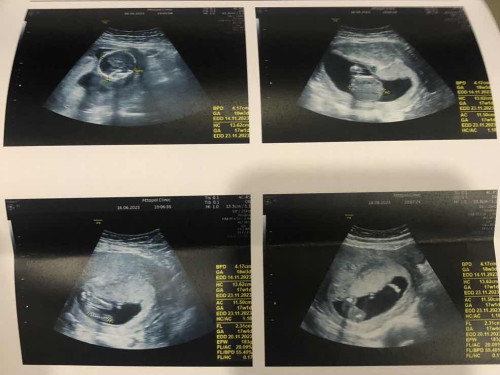

ทีม22 พ.ย คุณหมอบอกน่าจะผู้หญิงแต่ยังไม่ชัวร์ แม่ๆว่ายังไงบ้างค่ะ ส่วนเราดูไม่เป็นค่ะ 😁

ใครดูเป็นช่วยแม่ดูหน่อยค่ะ

น่าจะหญิงค่ะ😊